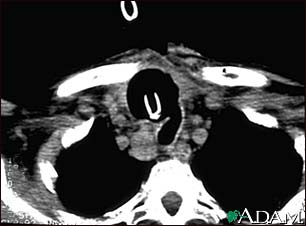

Thyroid cancer - CT scan

This CT scan of the upper chest (thorax) shows a malignant thyroid tumor (cancer). The dark area around the trachea (marked by the white U-shaped tip of the respiratory tube) is an area where normal tissue has been eroded and died (necrosis) as a result of tumor growth.